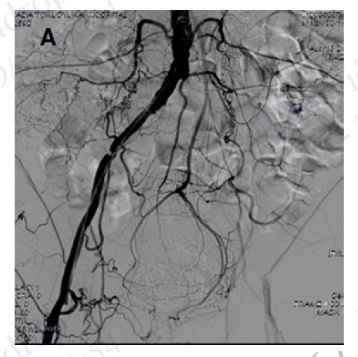

Hình 4.100. Chụp không chọn lọc ĐMC bụng và chụp chọn lọc động mạch thận trái cho thấy hẹp khít lỗ vào và đoạn gần động mạch thận trái

Hình 4.101. Loạn sản xơ cơ gây hẹp động mạch thận phải